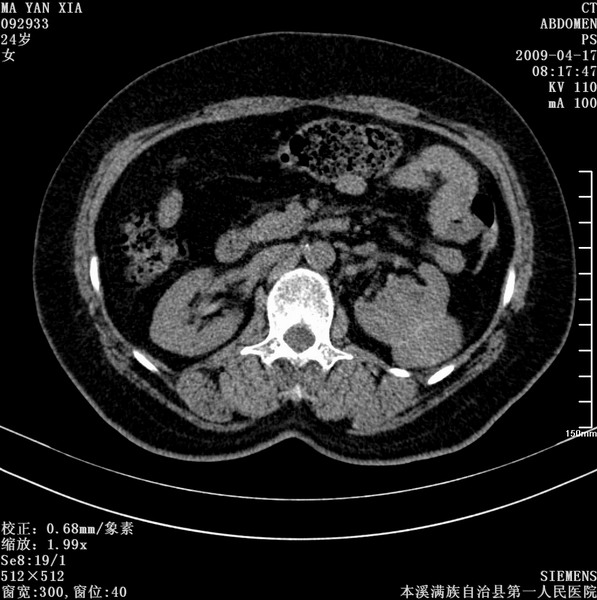

标题: CT19443:肾脏肿瘤两个区强化不一样。 [打印本页]

标题: CT19443:肾脏肿瘤两个区强化不一样。

女,51岁,体检时发现肾脏占位,建议ct增强。无任何自觉症状。

典型的不均匀强化,左肾癌